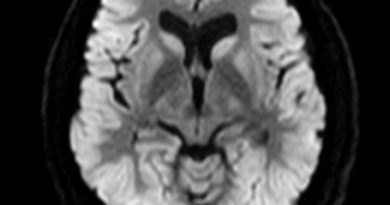

1. A) Her iki serebellar hemisferde simetrik sinyal artışları izlenmektedir (oklar).

2. B) Her iki serebral hemisferlerde sentrum semiovale ve periventriküler beyaz cevher alanlarında simetrik, U liflerinin korunduğu FLAIR sinyal artışları mevcuttur (ok).

3. C) Spinal kord seyri boyunca dorsal ve lateral kolonlarda simetrik sinyal artışları görülmektedir (oklar).

• Serebral beyaz cevherde, subkortikal U liflerinin korunduğu yama tarzında veya homojen birleşme eğilimi gösteren T2/FLAIR sinyal artışları

• Spinal kord dorsal ve lateral kortikospinal traktlarda simetrik T2/FLAIR sinyal artışları

• Medulla oblongata medial lemniskus dekussasyo düzeyinde ve/veya piramitlerde simetrik T2/FLAIR sinyal artışları

• Korpus kallosum splenium, internal kapsül posterior bacağı, süperior veya inferior serebellar pedinküller, trigeminal sinir intraaksielsegmentinde, anterior spinoserebellar trakt, medulla oblongata ve serebellar hemisferlerde T2/FLAIR sinyal artışları